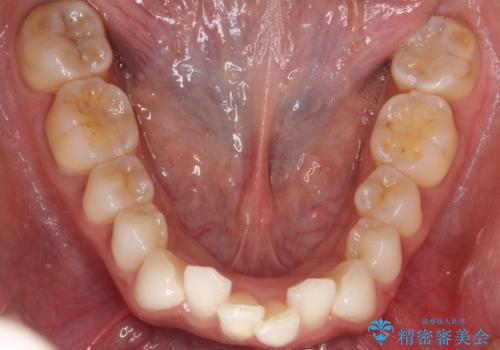

【インビザライン】前歯の凸凹をIPRで改善

- 前歯の凸凹を主訴に来院されました。

前歯を並べるために歯と歯の間にヤスリを入れてわずかに歯を削ることでスペースを確保しています。

歯と歯の間にヤスリを入れてわずかに歯を削ることでスペースを確保する処置をIPRと呼びます。

当院では拡大鏡を用いて丁寧に処置することで歯冠形態を損なわずに行うことができます。